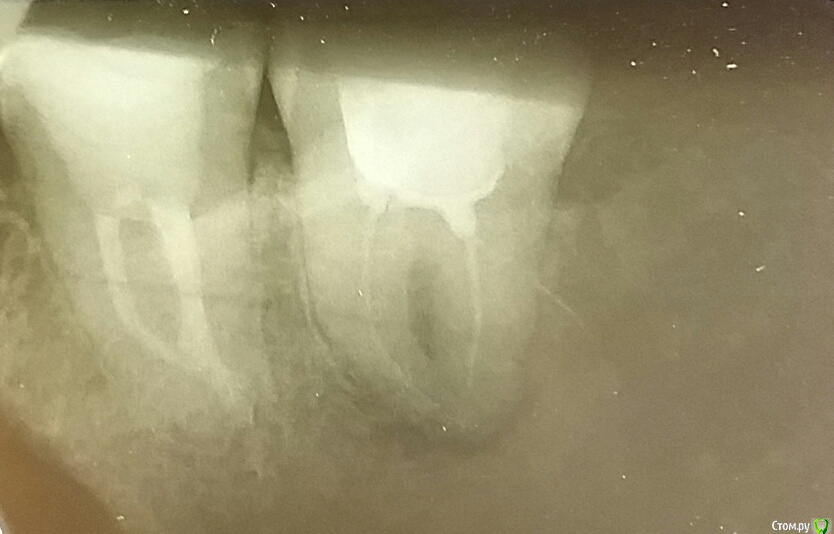

арбузова Опубликовано 11 октября, 2017 Автор Поделиться Опубликовано 11 октября, 2017 (изменено) Перелечила, все равно пока болит, не пойму как теперь состояние по снимкам, лучше? Не подскажете что делать? Подождать, может, перестанет или таки удалять? И как-то не нравятся с правой стороны от восьмерки разводы у зуба темные, что это дефект снимка? Изменено 11 октября, 2017 пользователем арбузова Ссылка на комментарий